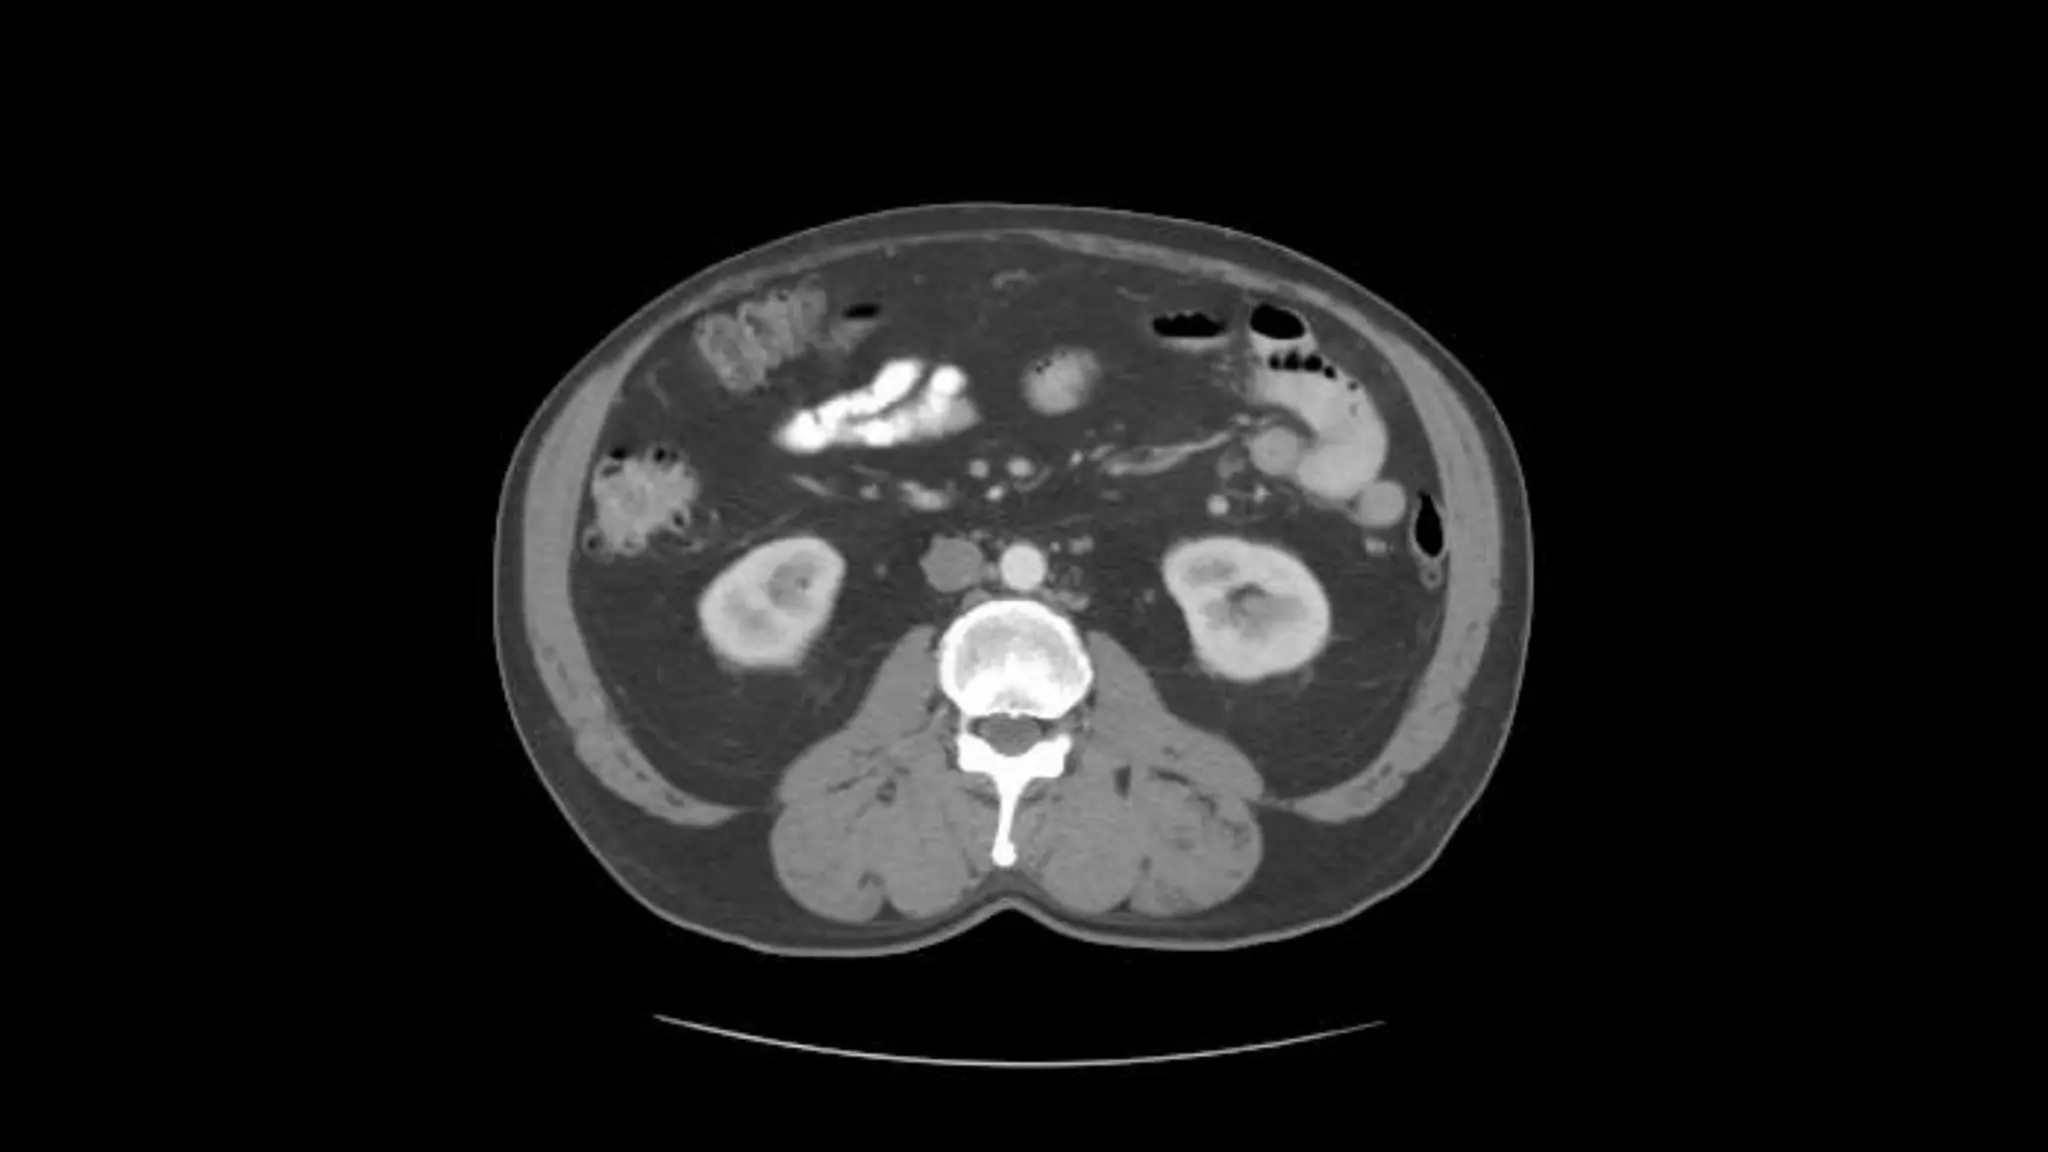

You can see the Celiac artery starting to branch from the

Aorta. You can follow this down in the next four images

Proper Hepatic Artery is labeled in the upper right The splenic

vein and artery are in the lower left

Proper Hepatic Artery and Splenic Artery

(the splenic artery is the circle).

Splenic Vein

Here the Splenic Vein is emptying into the portal vein.

Follow this up and down.

Pancreas

This is the Superior Mesenteric Artery branching

off the Aorta.